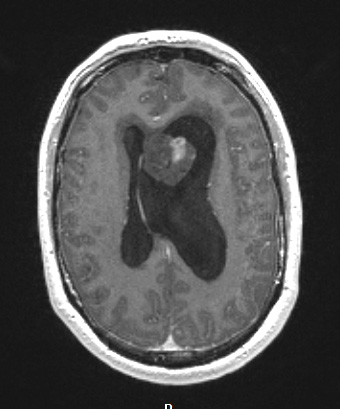

Washington University Experience | NEOPLASMS (GLIAL) | Subependymoma | 17A2 Subependymoma (Case 17) T1W

The T1-weighted image with administered contrast shows a neoplasm abutting the septum pellucidum with patchy contrast enhancement. Note the marked asymmetric hydrocephalus.